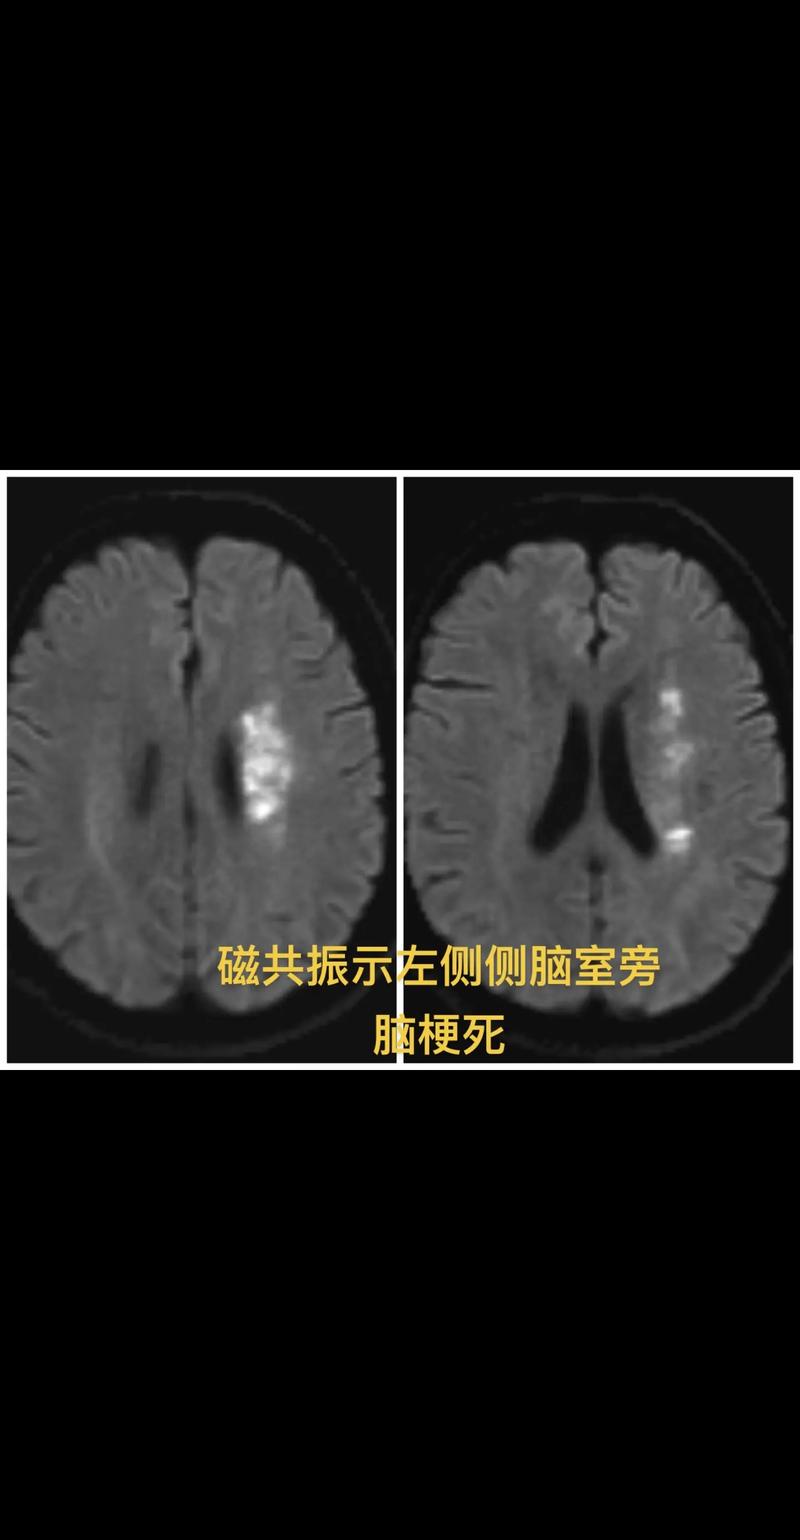

(图片来源网络,侵删)- 对于超早期的脑梗(<6小时),CT可能完全正常,此时需要更敏感的MRI(磁共振),特别是DWI序列来发现病灶。

- 对于非常新鲜的、极小的腔梗,CT可能也看不清,MRI对微小病灶的显示能力远优于CT。